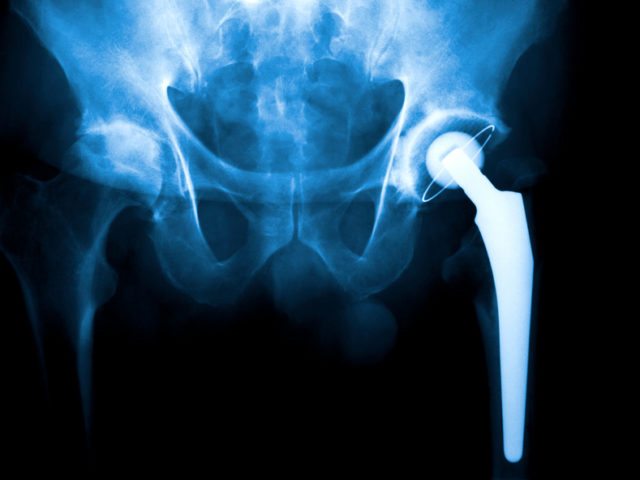

New Advancements in Technology Allows Joint Replacement Surgery to Thrive

Have you ever been so stiff and in so much pain that you had trouble with your mobility? Well, that pain and stiffness could be due to your joints. Joints can become damaged by arthritis, overuse, or from sustaining injuries. Arthritis or simply years of use may cause a lot of wear and tear on…

Hip Replacement Surgery

The hip joint is one the largest joints of the body that serves in the movement of the thigh, forward and backward. The hip joint also rotates when sitting, and with changes of direction while walking. The joint of the hip is where the ball of the thigh (femur) joins the pelvis at a socket…